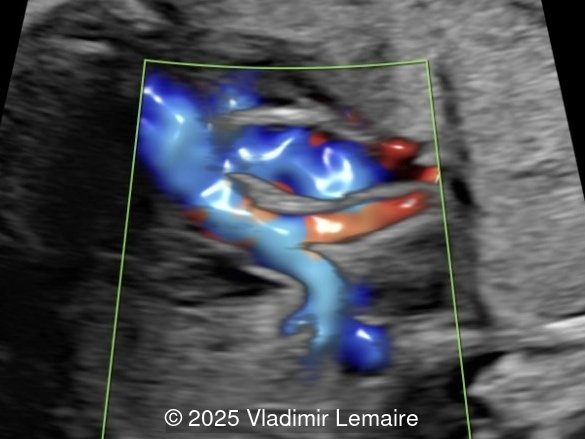

3D spatiotemporal image correlation (STIC) ultrasound volume displayed in glass-body mode at the level of the three-vessel-trachea view. Note the small size of the pulmonary artery as compared to the aorta with antegrade flow.

Image 3 3D spatiotemporal image correlation (STIC) ultrasound volume displayed in glass-body mode at the level of the three-vessel-trachea view. Note the small size of the pulmonary artery as compared to the aorta with antegrade flow.